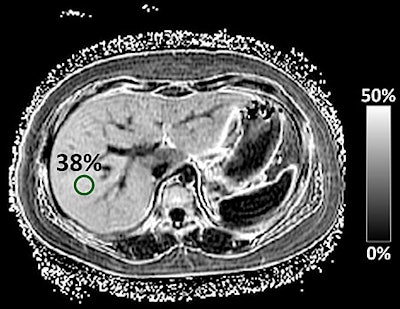

Each patient underwent a 3-tesla MRI scan to estimate liver proton density fat fraction. The mean time between the MRI and liver biopsy was 57 days (± 51 days). The MRI results were compared with pathology from the conventional liver biopsy.

The researchers found a strong correlation (0.72) between the amount of liver fat measured by the new MRI technique and the degree of liver fat determined by pathology. The correlation was stronger among girls (0.86) than boys (0.70), and it was weaker in patients with stage 2 to 4 fibrosis (0.61) than in children with no fibrosis (0.76) or stage 1 fibrosis (0.78).

Using threshold values of 0.69 to 0.82 to distinguish between no fat concentration and mild fat concentration in the liver, the MRI-estimated liver proton density fat fraction was able to predict the histologic degree of fat concentration with an overall accuracy of 56%.